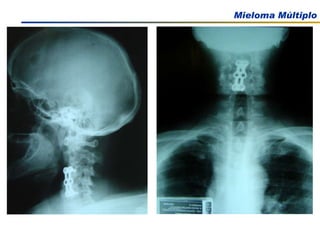

Comprometimento Ósseo

EXAMES COMPLEMENTARES Rx de esqueleto Em casos selecionados: TAC, RNM NCCN Practice guidelines in Oncology – v 2.2009

Dor ossea Presente em 2/3 dos pacientes com mieloma: dorso e tórax Agravada pelo movimento. Dor persistente pode indicar fraturas nas vértebras Manifestações clínicas Medeiros, C. R in Zago, M.A et al, Hematologia; fundamentos e prática, 2001 Hoffman Hematology 5th Edition, 2008

Dor ossea Presenteem 2/3 dos pacientes com mieloma: dorso e tórax Agravada pelo movimento. Dor persistente pode indicar fraturas nas vértebras Manifestações clínicas Medeiros, C. R in Zago, M.A et al, Hematologia; fundamentos e prática, 2001 Hoffman Hematology 5th Edition, 2008